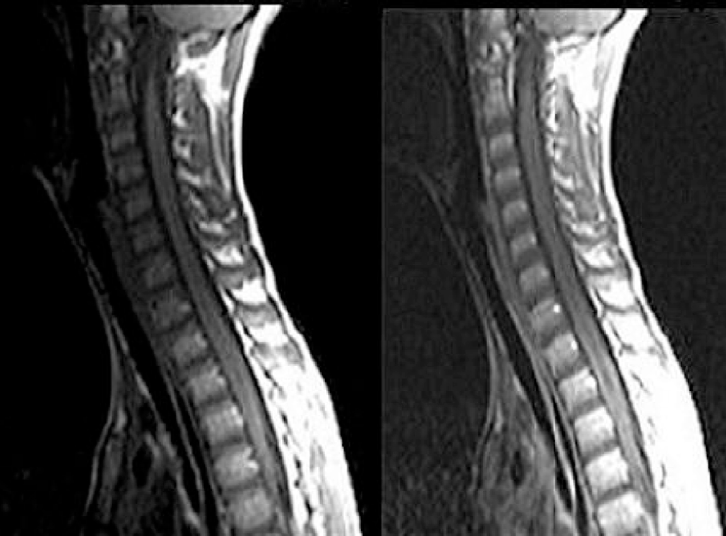

Presentamos el caso de un varón de 10 años sin antecedentes de interés, con gonalgia bilateral, dorsalgia y lumbalgia tras caída de una bicicleta hace 4 días. A la exploración presentaba una movilidad activa y pasiva conservada con dolor en ambos miembros inferiores (MMII). No se observaron datos de fracturas ni alteraciones neurológicas. Se pautó reposo deportivo, frío local y tratamiento antiinflamatorio. A las 48 horas, el paciente acu de nuevamente por persistencia del dolor, pérdida de fuerza, parestesias en MMII, dificultad para incorporarse y deambular e incontinencia urinaria. La exploración física reveló una disminución de la fuerza y una alteración de la sensibilidad en ambos MMII. Ante la sospecha de mielitis transversa se derivó al paciente al servicio de urgencias hospitalario. Durante su ingreso la analítica sanguínea resultó normal, el estudio del líquido cefalorraquídeo reveló una moderada pleocitosis, sin presencia de bandas oligoclonales de IgG; el electroencefalograma no evidenció alteraciones y los potenciales evocados demostraron una parálisis y espasticidad de MMII, hiporreflexia y Babinsky bilateral, ausencia de reflejos abdominales y cremastéricos, hiperalgesia y disestesia del tronco y MMII. El electromiograma reveló una alteración de la sensación somatosensorial medular a través de los cordones posteriores, sin conducción a través del cordón derecho y con alteración parcial del cordón izquierdo. La resonancia magnética (RM) cerebral resultó normal, sin embargo, la RM medular mostró una lesión expansiva a nivel medular desde D1 a D6 compatible con mielitis transversa (figura 1).

Ante la presencia de mielitis transversa y neuritis óptica, con RM cerebral que no cumplía criterios de esclerosis múltiple y RM medular que muestra una lesión de tres o más segmentos medulares (D1 a D6), se realizó estudio del anticuerpo antiacuoporina-4, que fue negativo. De acuerdo con la clínica, evolución y pese a la negatividad del anticuerpo, se diagnosticó al paciente de neuromielitis óptica o enfermedad de Devic (ver criterios diagnósticos tabla 1).